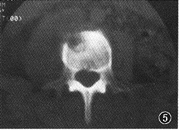

(2)CT檢查採用靜脈注射造影劑增強後,可顯示出5mm大小的垂體腺瘤。更小的腫瘤顯示仍有困難。